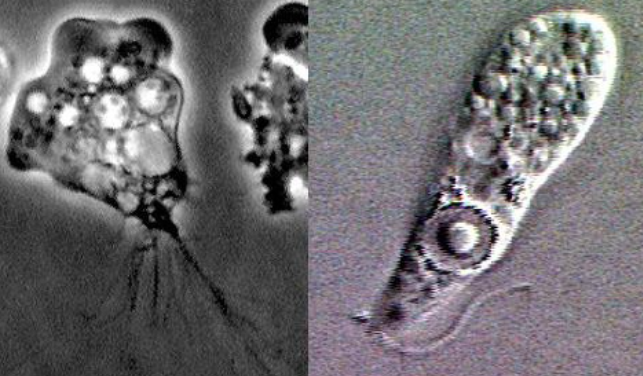

파울러자유아메바(Naegleria fowleri) 관련 이미지. 위키피디아

병원 측은 정밀 검사를 통해 A양이 파울러자유아메바 감염에 의한 원발성 아메바성 수막뇌염 진단을 받았다고 밝혔다. 파울러자유아메바는 단세포 원생동물의 일종으로, 주로 여름철 따뜻한 담수 환경에서 서식한다. 호수, 강, 온천, 인공 수영장 등 30도 이상의 따뜻한 물에서 활동성이 강해지며, 특히 정체된 물에서 감염 가능성이 높다.

사람이 이 아메바에 감염되는 주요 경로는 코를 통한 침투다. 물놀이 중 물이 코를 통해 흡입되면 아메바가 후각 신경을 따라 뇌로 이동, 뇌 조직을 파괴한다. 이 과정에서 뇌에 심각한 염증과 부종을 유발하며, 이 때문에 ‘뇌를 먹는 아메바’라는 별명으로 불린다.